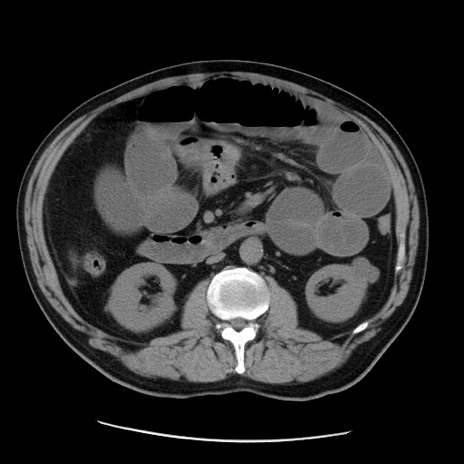

症例20(横断像)

【症例】 60歳代男性

【主訴】 腹部膨満、嘔吐

【現病歴】5日前頃より倦怠感を認め食事量減少し4日前の朝嘔吐、食事摂取困難となった。 3日前近医受診し点滴施行され整腸剤などを処方された。 当日他院を受診し、腹部膨満著明、炎症反応の上昇(CRP10.8、WBC11200)あり、紹介受診となる。

【身体所見】 意識JCS1 受け答えがはっきりしないBP 111/57mHg、 P 67bpm、、BT35.2°C、SpO2 97%(RA)、 腹部:膨隆、打診で鼓音あり、全体的に圧痛有り、腸蠕動音(-)、反跳痛ははっきりせず。

【データ】WBC 11400、CRP 14.20